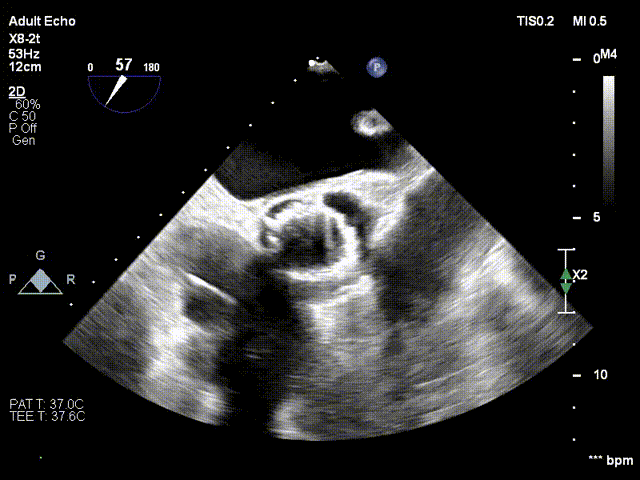

病例概览

患者病史 男性,74y, 因 “发现心脏瓣膜病 1 年,加重伴喘气半年” 入院。门诊检查显示主动脉瓣重度AS并伴轻-中度AR。患者基础疾病较多:胸腹主动脉多发穿透性溃疡、心功能III级等,手术指征明确,但风险极高。 术前CT LVOT- Annulus 倒梯形,对植入瓣膜有挤压位移风险,Annulus直径23.7mm,瓣叶增厚,钙化集中在无冠窦边缘。 左冠脉开口高度可,瓣叶不长、窦部空间较大,无冠脉风险;室间隔膜部较短,有一定PPI风险,心脏角度37.9°;心室较小,有一定循环崩溃风险,术前注意补液。 术前造影角度及入路:血管入路散在钙化、无迂曲;主动脉弓条件好、双侧股动脉直径大、右股穿刺点侧壁存在环形钙化 左右重合位:RAO 7° CAU 21° 右窦中心位:LAO2 1° CAU 1° 手术策略 20mm球囊预扩后植入AV26瓣膜,同时做好预防循环崩溃、传导阻滞的应急预案。 术中挑战 1)球囊预扩:20mm球囊预扩时无明显 “腰征”,但存在少量反流,提示瓣膜钙化与解剖结构对扩张的阻力不均 2)首次释放偏差:第一次定位释放时,瓣膜在 “开花” 过程中下滑约 3mm,工作位观察显示小弯侧瓣周漏较多(深度超过完全覆膜区),需二次调整。 3)二次精准定位:以猪尾导管为参照,将定位点调整至 “猪尾 - 2mm” 处,结合真实窦底深度(较深)重新释放,最终瓣膜位置稳定,瓣周漏显著减少。 术后即刻效果: 瓣膜形态良好,跨瓣压差从术前的 67mmHg 降至 6mmHg,且无明显瓣周漏,冠脉开口通畅; Commisural Alignment 术后即刻超声: Prostyle A®预装干瓣——助力临床最优化解决方案: √ 平衡的径向支撑力:特殊的解剖结构下位置形态良好,术后跨瓣压差大幅降低,血流动力学改善明显; √ 80%可回收设计:支持术中二次调整释放位置,保证精准释放; √ 平衡的收腰设计&Commissural Alignment设计: 为患者后期冠脉PCI保留了生命通道;